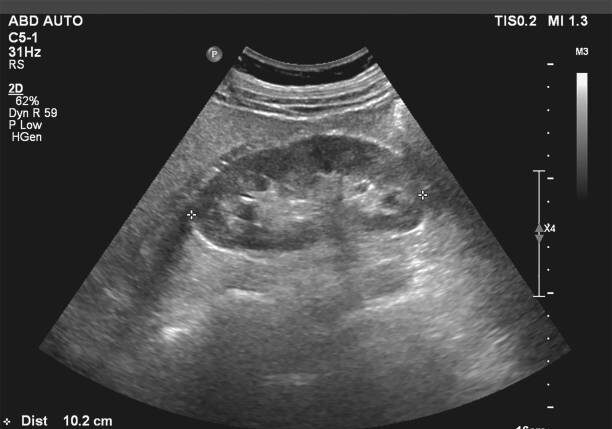

·       Abdominal (hígado, vesícula biliar, vía biliar, bazo, riñones)

Ecografía abdominal

Tiene que venir en AYUNAS de 6 HORAS.